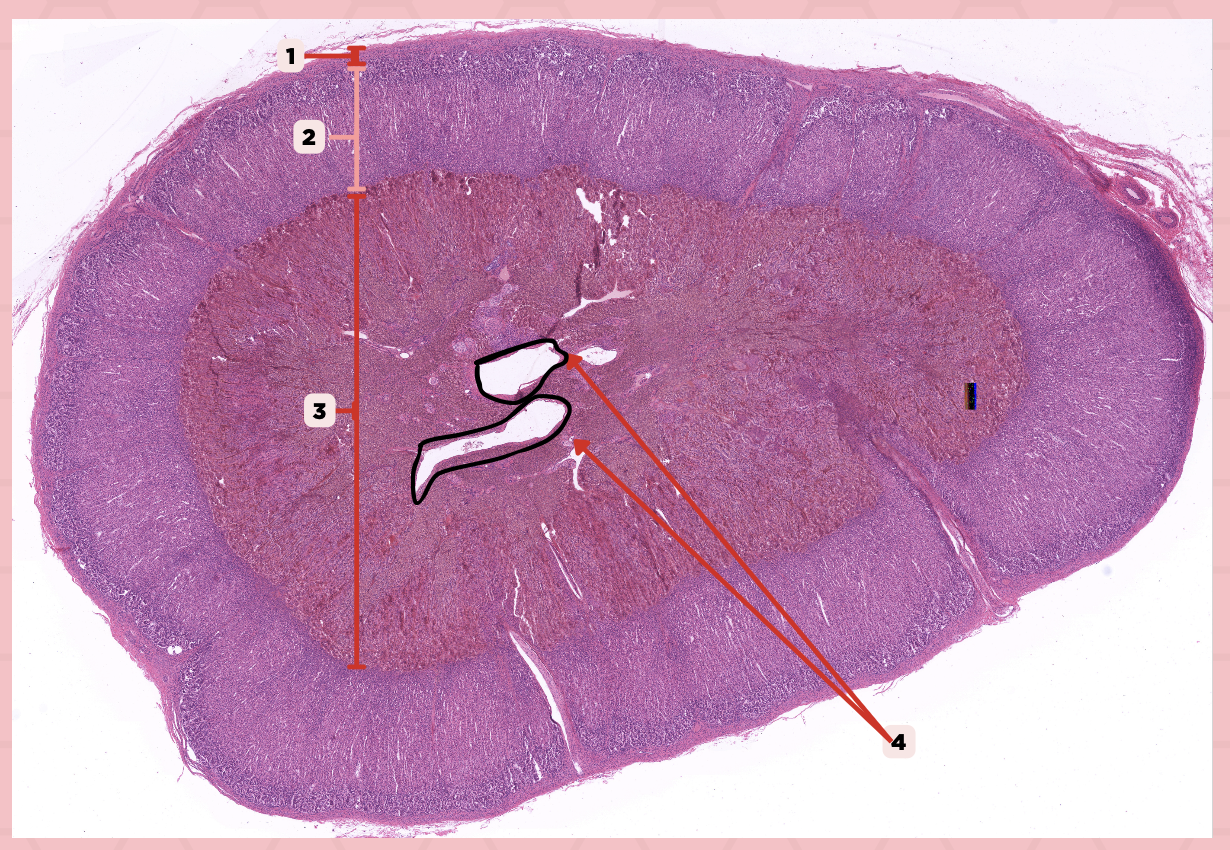

Adrenal

Identify the specimen.

Connective Tissue Capsule

Identify the structure labeled as 1.

Cortex

Identify the structure labeled as 2.

Medulla

Identify the structure labeled as 3.

Medullary Veins

Identify the structure labeled as 4.

Zone glomerulosa, Zone fasciculata, Zona reticularis

What are the zones present in pointer #2?

Catecholamines

What hormones are produced by pointer #3?